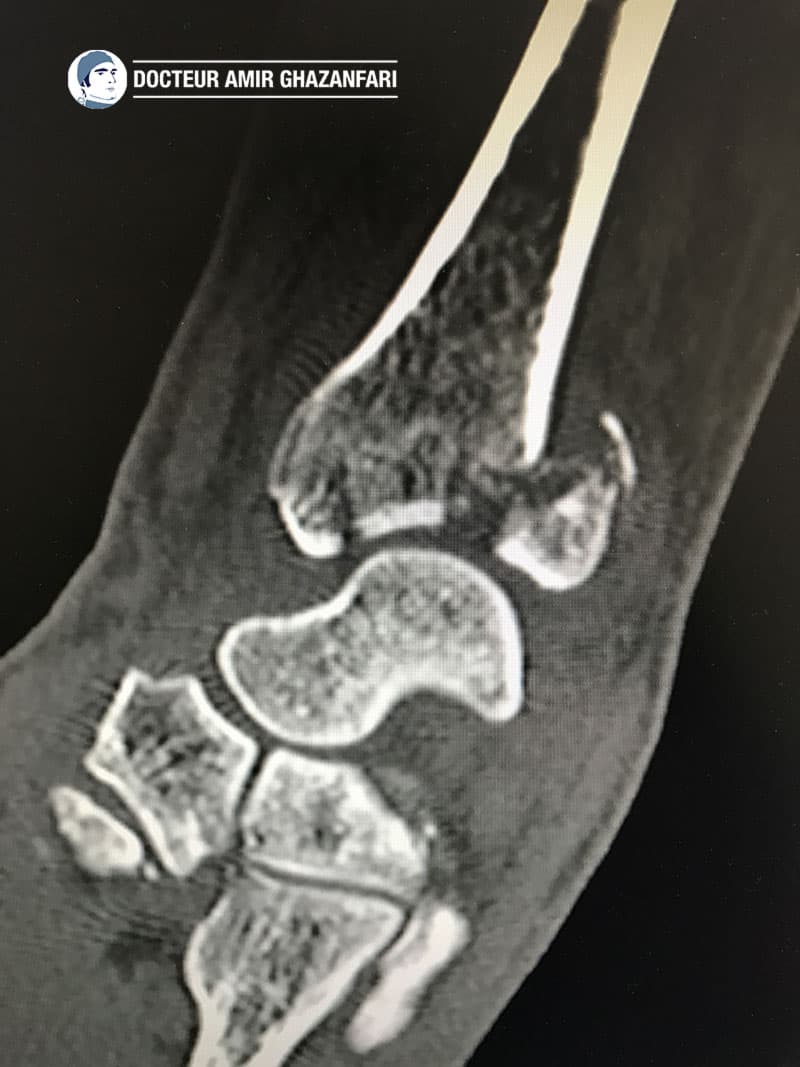

Si le patient présente une fracture complexe et/ou articulaire du radius, alors le scanner est indiqué (figure 5).

Figure 5. Scanner du poignet mettant en évidence une fracture articulaire du radius